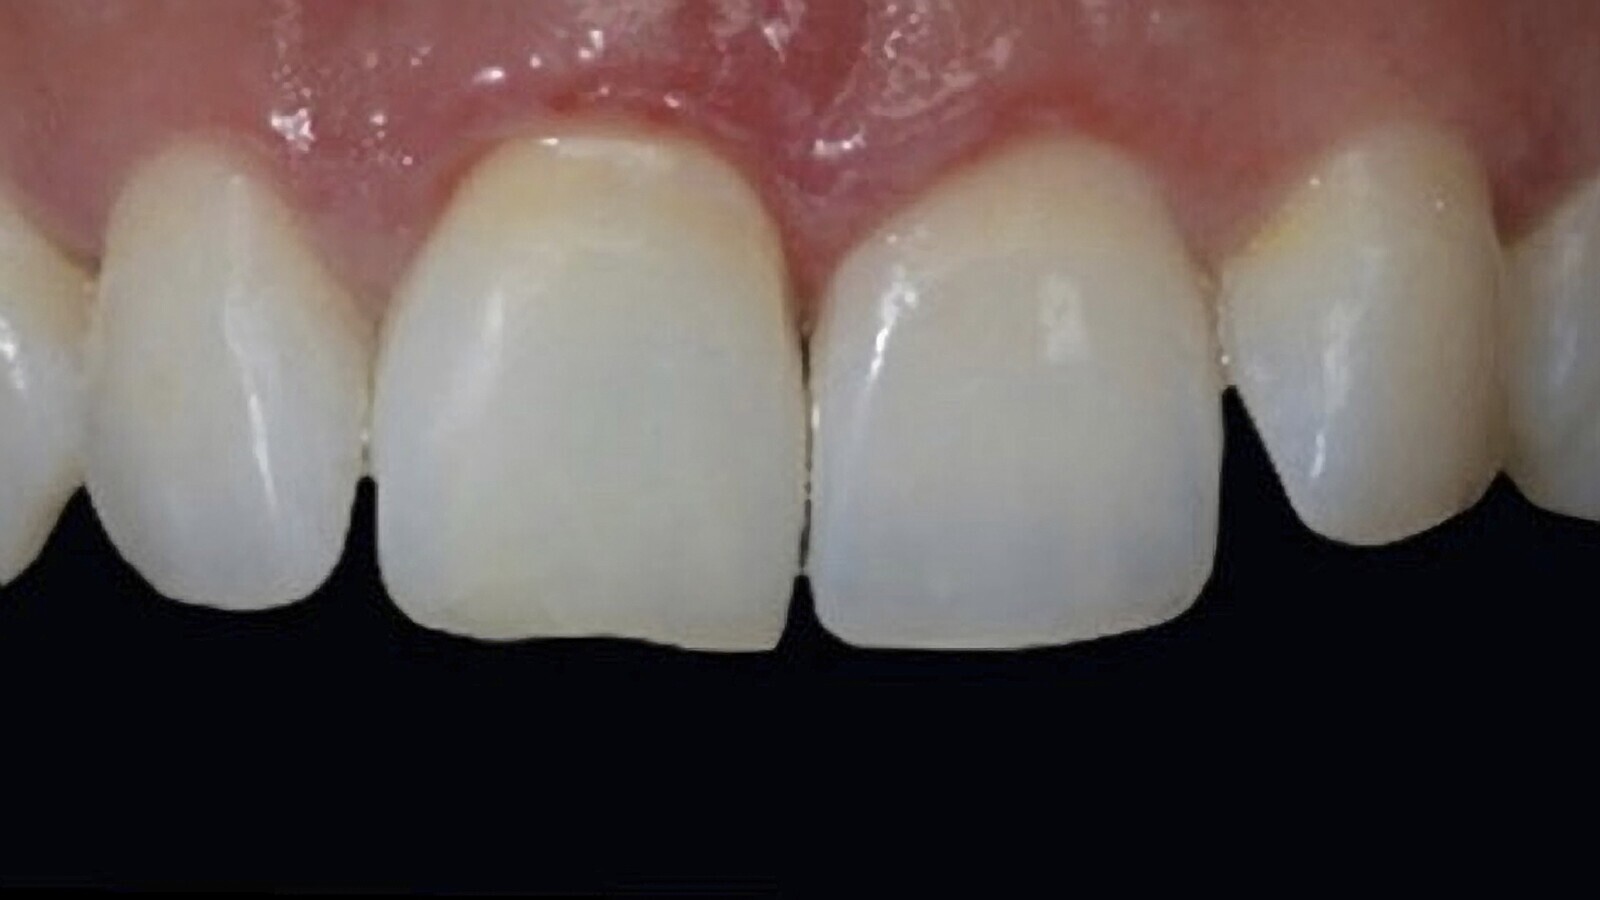

Figura 1B. La desarmonía de la imagen superior fue solucionada mediante un tratamiento de blanqueamiento combinado.

Figura 2B. Postoperatorio luego del blanqueamiento interno y externo ambulatorio y el cambio de las restauraciones de resina filtradas.